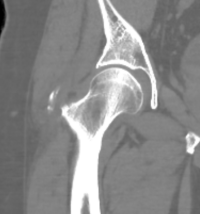

55-åring med snabbt insättande mycket kraftig smärta i höger höft, spontant återställd efter ett par dagar

Två exempel på kalkaxlar, både med kraftig smärta och förhöjt CRP men återställda efter några dagar.